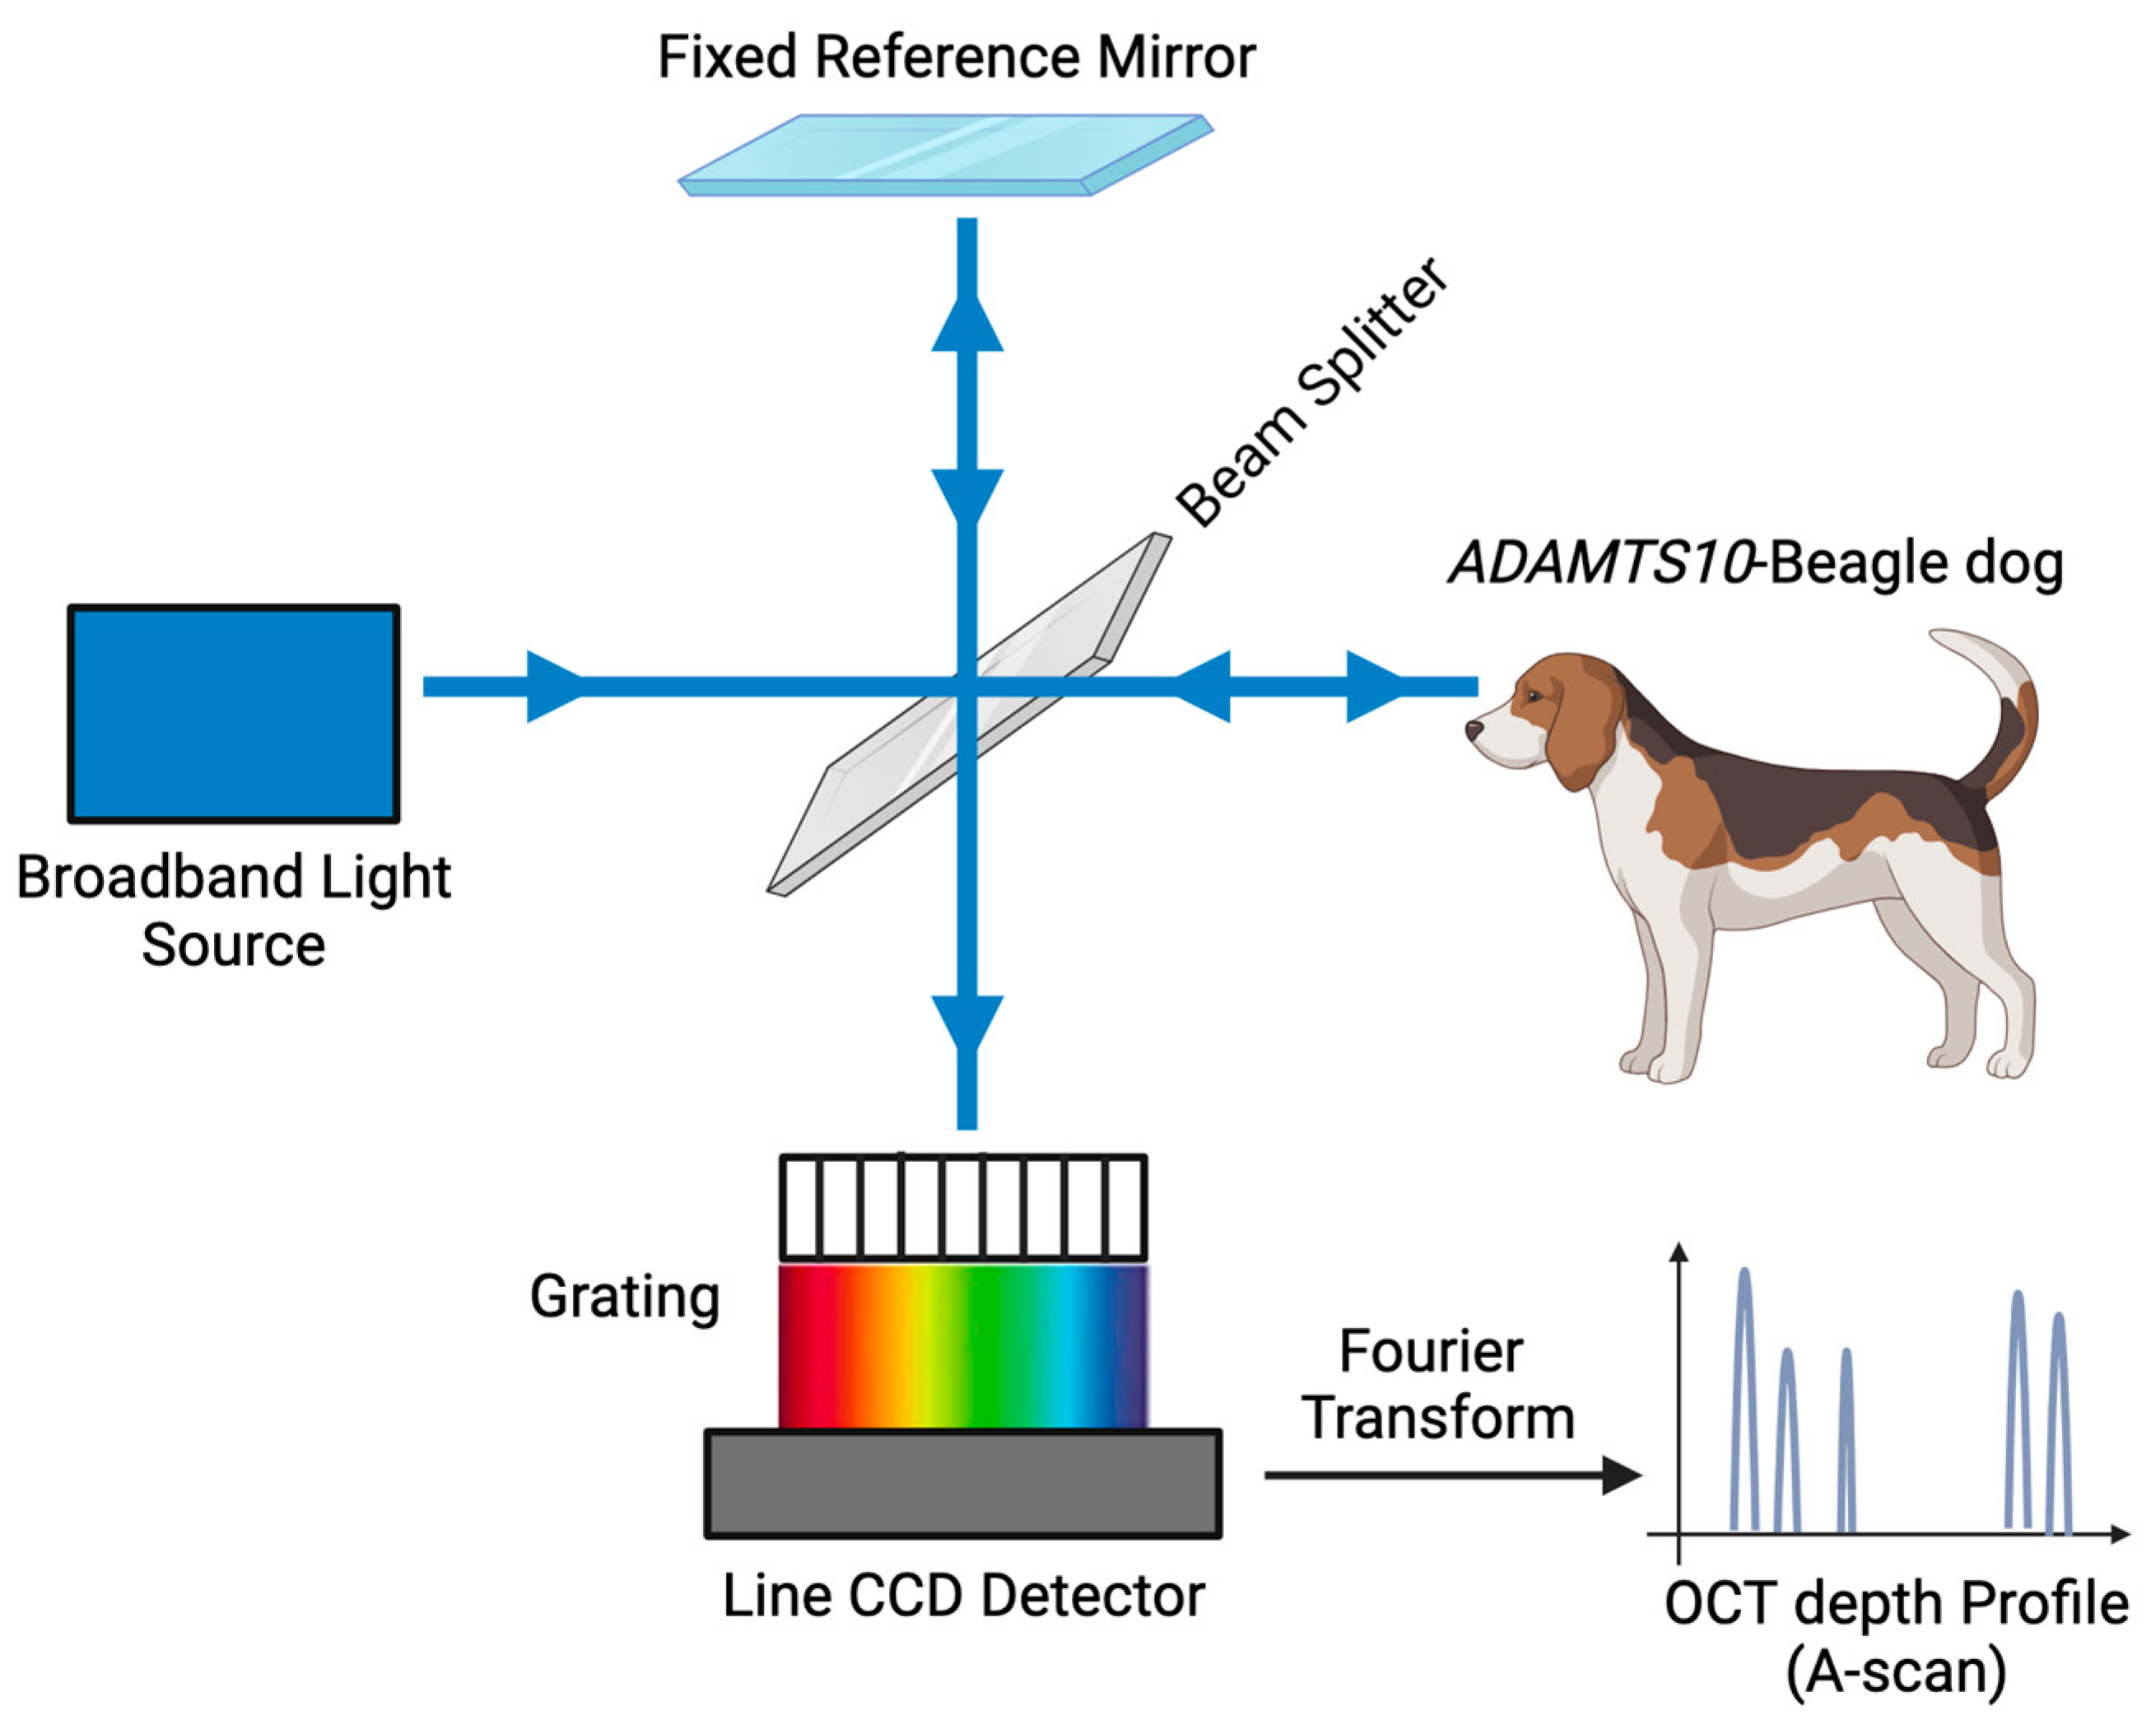

2.3. Spectral-Domain Optical Coherence Tomography (SD-OCT) Image Acquisition

- Zheng, S.; Bai, Y.; Xu, Z.; Liu, P.; Ni, G. Optical Coherence Tomography for Three-Dimensional Imaging in the Biomedical Field: A Review. Front. Phys. 2021, 9, 744346. [Google Scholar] [CrossRef]